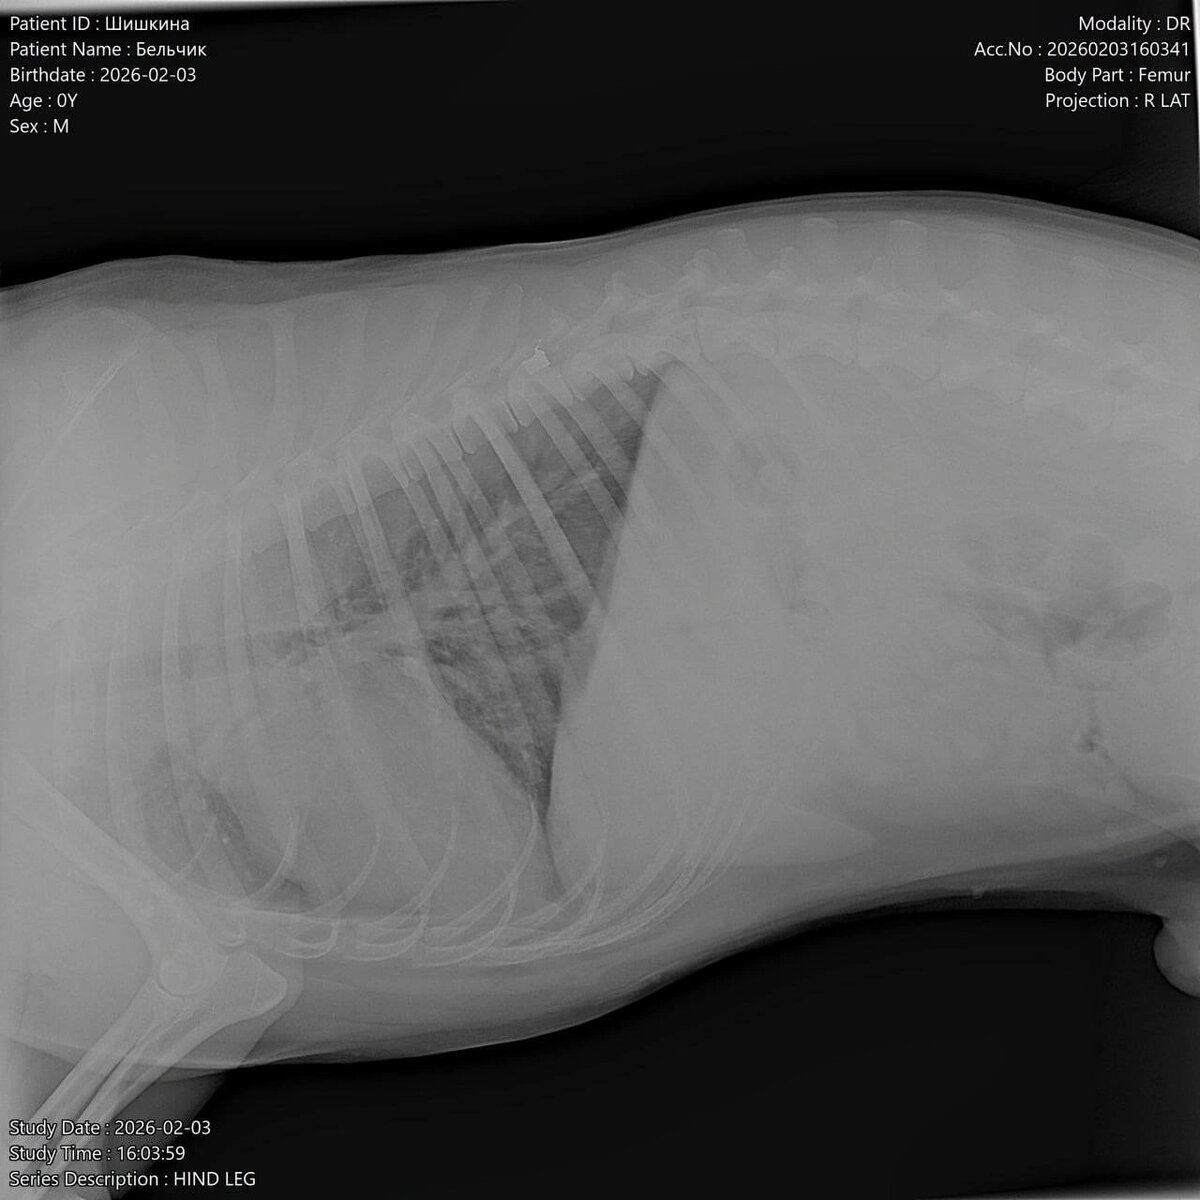

Сегодня, 4 февраля, в социальных сетях азовского приюта «Феникс» появилась информация о том, что днем ранее возле трассы рядом с кафе «Дорожное» была найдена собака, метис хаски или лайки, которая лежала и не двигалась. Изначально никаких повреждений визуально очевидцы не обнаружили, поэтому решили, что пса сбил автомобиль. Однако потом стало понятно, что животное не может встать на задние лапы и тянет их за собой. Собаку привезли в ветклинику: рентген показал, что у пса пуля в позвоночнике и перелом таза. «Что случилось, страшно представить, подстрелили, потом сбила машина... Бедное животное из последних сил выползло к людям в надежде на помощь. Просим правоохранительные органы отреагировать на ситуацию. Это не единственный случай на Мичуринце 3. Вместо того, чтобы вызвать отлов на собачью свадьбу, кто-то стреляет в собак, превращая их в пожизненных инвалидов. Собака может никогда не встать на лапы. Пёс добрый, адекватный. За что с ним так поступили и бросили в -15 на морозе», – нап

Сегодня, 4 февраля, в социальных сетях азовского приюта «Феникс» появилась информация о том, что днем ранее возле трассы рядом с кафе «Дорожное» была найдена собака, метис хаски или лайки, которая лежала и не двигалась. Изначально никаких повреждений визуально очевидцы не обнаружили, поэтому решили, что пса сбил автомобиль. Однако потом стало понятно, что животное не может встать на задние лапы и тянет их за собой. Собаку привезли в ветклинику: рентген показал, что у пса пуля в позвоночнике и перелом таза.